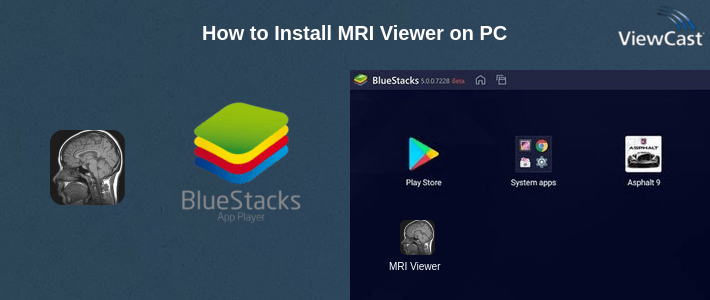

MRI Viewer is primarily a mobile app designed for smartphones. However, you can run MRI Viewer on your computer using an Android emulator. An Android emulator allows you to run Android apps on your PC. Here's how to install MRI Viewer on your PC using Android emuator:

Visit any Android emulator website. Download the latest version of Android emulator compatible with your operating system (Windows or macOS). Install Android emulator by following the on-screen instructions.

Launch Android emulator and complete the initial setup, including signing in with your Google account.

Inside Android emulator, open the Google Play Store (it's like the Android Play Store) and search for "MRI Viewer."Click on the MRI Viewer app, and then click the "Install" button to download and install MRI Viewer.

You can also download the APK from this page and install MRI Viewer without Google Play Store.

You can now use MRI Viewer on your PC within the Anroid emulator. Keep in mind that it will look and feel like the mobile app, so you'll navigate using a mouse and keyboard.